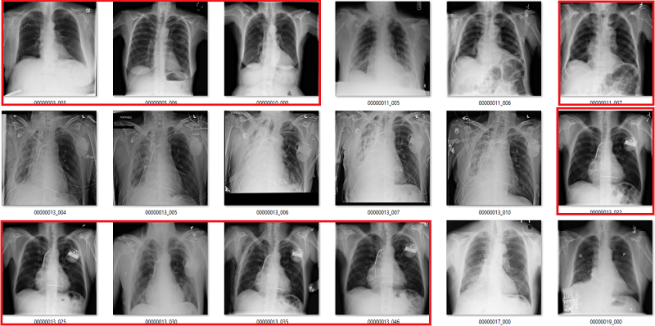

What follows is a bunch of pictures based on the labels in the dataset. In this case, they are pseudo-random. Like I said, it doesn’t have to be perfect. They are randomly chosen sequential sets of 18 images. They are not cherry-picked.

Also, I have tried to err on the side of caution, in the sense that I favour the label class when a case is equivocal.

In all the images, red = clearly wrong label. Orange = I doubt it, I wouldn’t report it, but I can’t really exclude it. Correlate clinically :p

Atelectasis

Cardiomegaly

Fibrosis

My labels aren’t perfect. Other radiologists will disagree with some of them, and the reduced resolution doesn’t help. But it should be clear that my labels and the results presented in the paper/supplement are vastly different.

I always like hard numbers, so I did my best to quantify the label accuracy where I can. I actually found it very hard to define many of the labels, which is why they are not listed below. I reviewed ~130 images in each class, and calculated the accuracy of the original labels according to my visual interpretation. This is a pretty good amount of data to use, as the 95% confidence intervals will probably be less than +/- 5%, even allowing myself up to a 20% error rate.

Visual analysis by me. Text mining results from the paper.

Again, I doubt my labels are “right” compared to some form of fairly reliable ground truth (like a panel of chest radiologists), but the difference here is stark. I think that these findings make a strong case that these labels do not appear to visually match the diseases they should represent.